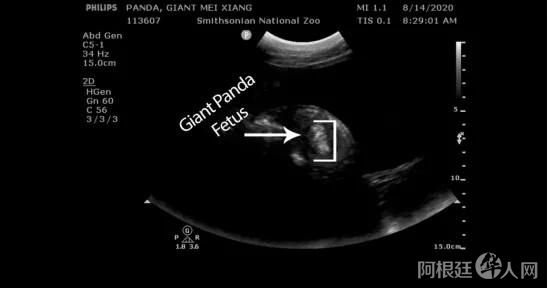

上周,位于华盛顿的美国国家动物园宣布,他们在14日早上为大熊猫美香进行了超声波检查,图像清楚地拍到了看起来像是胎儿的物体。动物园首席兽医Don Neiffer表示,甚至可能是两个胎儿。

美国国家动物园公布了美香的超声检查图像,疑似发现胎儿。(图片来源:美国国家动物园官网)